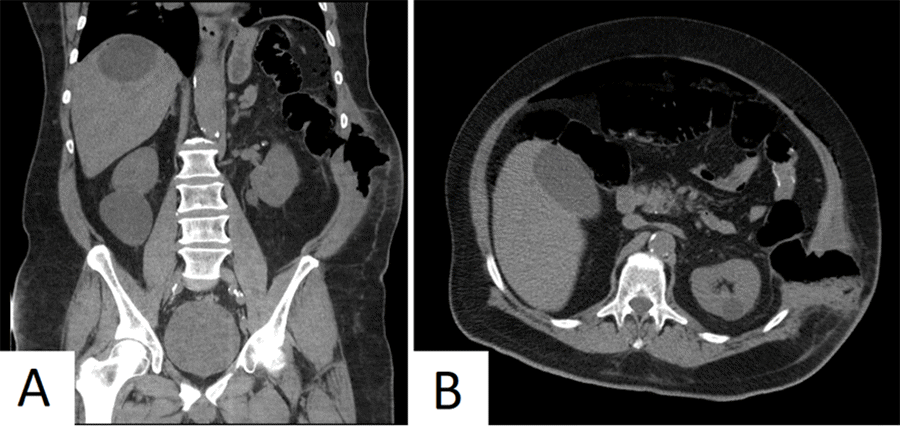

The patient's postoperative course was complicated by atelectasis and postoperative edema of the remaining lingular segments of the left upper lobe requiring diagnostic bronchoscopy on postoperative day (POD) 1 and steroid taper starting at 40 mg daily and dropping by 10 mg every 48 hours. He was discharged to rehab on POD 5 in stable condition while still on his steroid taper, with follow-up scheduled for POD 14. On POD 10, the patient was seen at an outside hospital with a chief complaint of abdominal pain, worsening erythema, and swelling of the left flank with purulent drainage that had been present for five days. He had bowel movements after discharge with no abdominal pain until two days before presentation. A computed tomography (CT) scan showed pneumoperitoneum, subcutaneous emphysema of the left flank, and herniation of the colon into the abdominal wall (Figure 1).

Figure 1. CT Scan of the Abdomen and Pelvis. Published with Permission

Note colonic perforation into abdominal wall and intraperitoneal contamination in A) coronal plane and B) axial plane